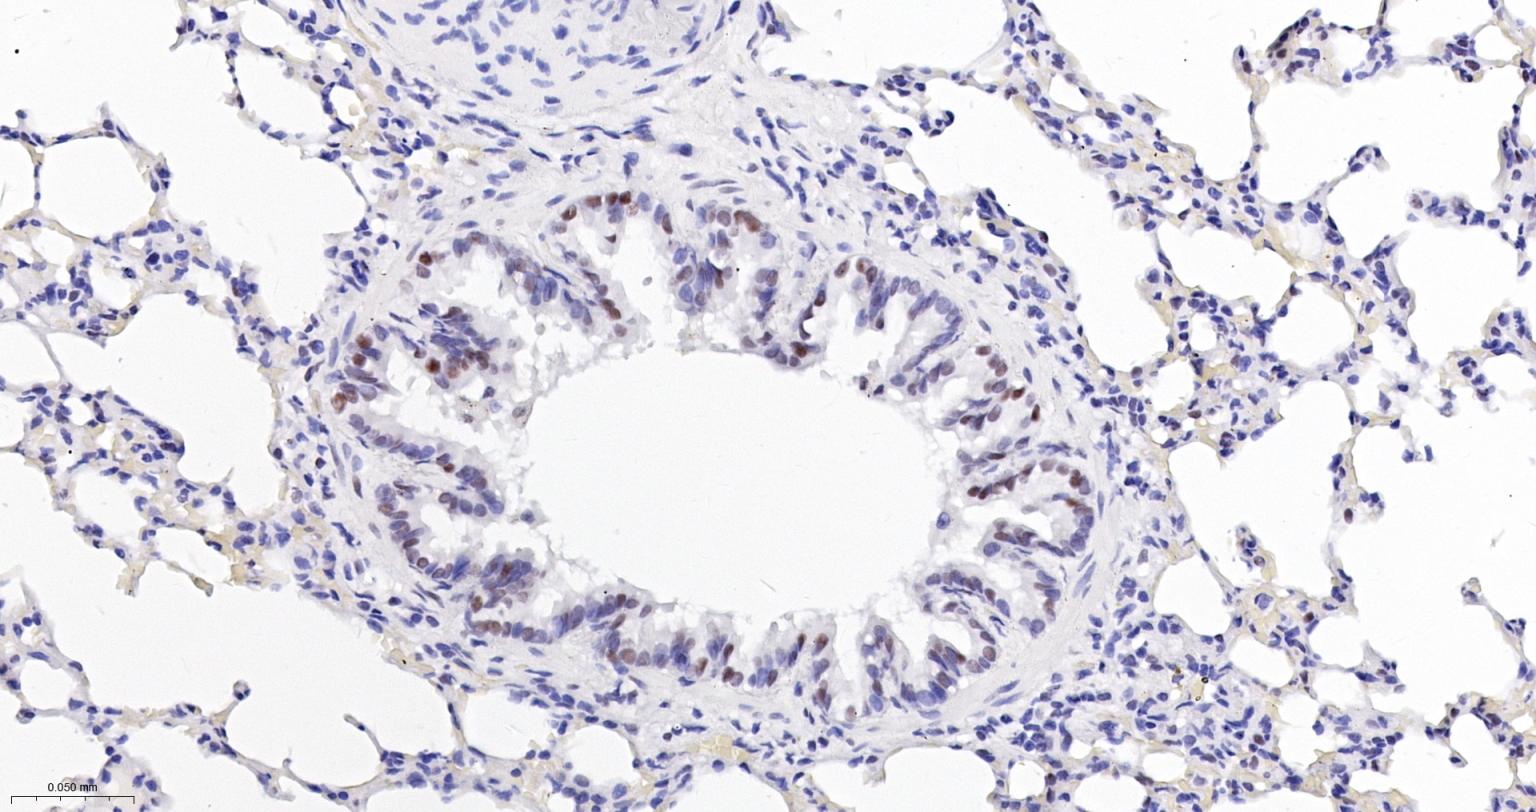

Paraformaldehyde-fixed, paraffin embedded Human Lung; Antigen retrieval by boiling in sodium citrate buffer (pH6.0) for 15 min; The section was incubated with USP39 Monoclonal Antibody, Unconjugated (bsm-63016R) at 1:200 overnight at 4°C, followed by conjugation to the bs-0295G-HRP and DAB (C-0010) staining.